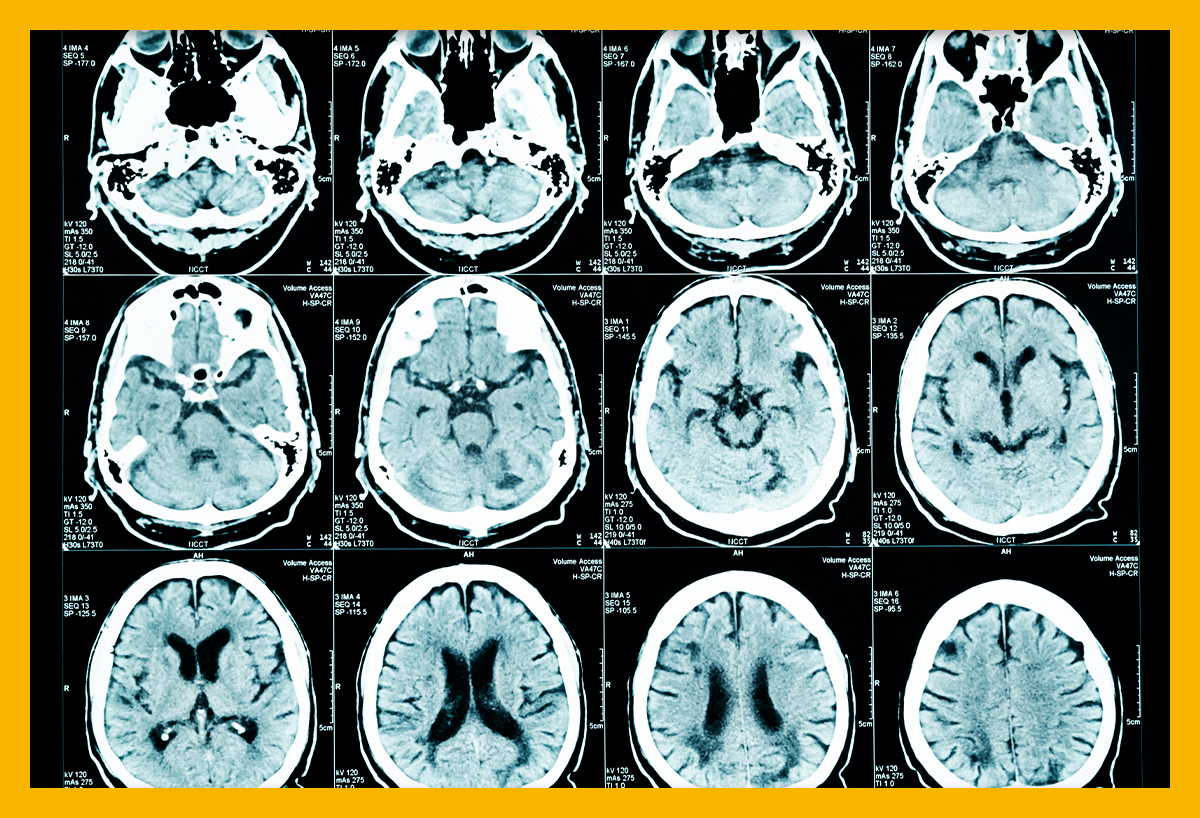

먼저 뇌경색이 무엇인지에 대해 쉽게 설명드리겠습니다. 뇌경색은 뇌로 가는 혈류가 차단되어 발생하는 질병으로, 일반적으로 뇌졸중이라고도 알려져 있습니다. 뇌혈관이 좁아지거나 막히면서 뇌가 필요한 산소와 영양분을 공급받지 못하게 되고, 이로 인해 뇌세포가 손상됩니다. 이러한 손상은 즉각적인 신체 기능 저하를 초래할 수 있으며, 심각한 경우 생명에 지장을 줄 수 있습니다.